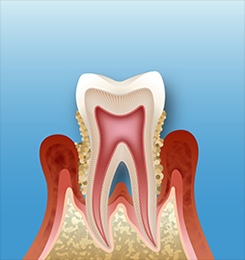

近年CMなどで良く耳にするようになった「歯周病」。実は、現在歯を失う原因で最も多いのは、虫歯ではなく、この歯周病です。特に30歳~40歳からは、歯周病で歯を失う比率が高まっていきます。 当院では、歯周病の原因となる歯石と歯垢を完全に取り除き、ぐらつく歯を抜かずに保存する方法で治療いたします。